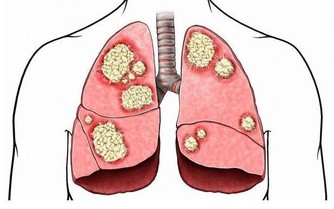

*****2、病毒侵犯心臟****

即便是身體健壯,若是出現流行性感冒或者是病毒性腹瀉,那麼就要當心了,因為這一部分患者中約有4%的人會被病毒侵犯心臟。如果還連續熬夜,過度疲勞,免疫力還會下降,就更容易被病毒侵犯。

一旦病毒侵犯心臟傳導系統,那麼可會引起嚴重心律失常,嚴重的甚至室顫,最終猝死。

所以呢,中青年要是感冒了,要注意休息,調養身體,切不能忽視,更不可“硬抗”

如果感冒伴有發燒,那就更要多加警惕,及時去醫院就診治療。